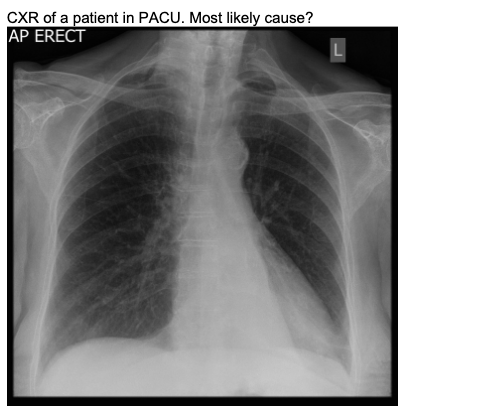

20.1 A 45-year-old man has poor oxygenation in the post anaesthesia care unit after a low anterior resection. His chest x-ray is below. The most likely diagnosis is

a) Left pneumothorax

b) Right pneumothorax

c) Left lower lobe collapse

d) Right lower lobe collapse

e) Normal XR